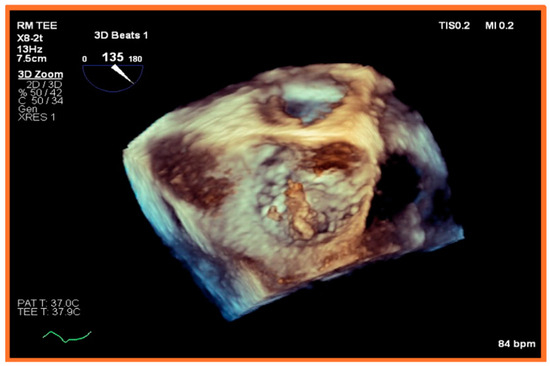

5.2. Transesophageal Echocardiography (TEE)